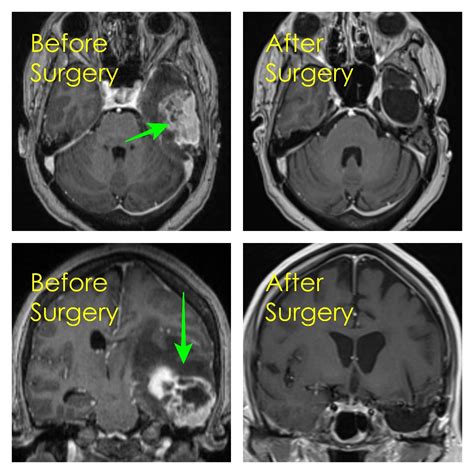

Diagnosing a brain tumor typically involves a combination of imaging tests, such as magnetic resonance imaging (MRI) and computed tomography (CT) scans. These tests help doctors determine the size, location, and type of tumor, which is crucial for planning the Brain Mass Removal procedure.

• Imaging Studies: Detailed imaging studies, such as MRI and CT scans, are reviewed to map the tumor's location and plan the surgical approach.

During the surgery, neurosurgeons use advanced imaging technologies, such as intraoperative MRI, to guide the procedure and ensure that as much of the tumor is removed as possible while minimizing damage to healthy brain tissue.

• Image-Guided Surgery: Advanced imaging technologies, such as intraoperative MRI and CT scans, provide real-time guidance during surgery, allowing surgeons to precisely locate and remove the tumor while minimizing damage to healthy tissue.